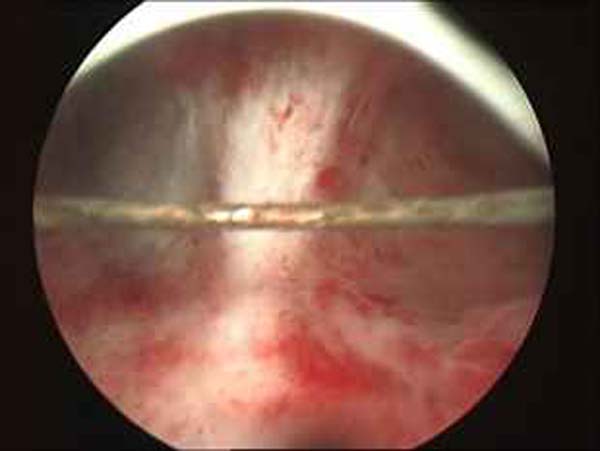

- Hystéroscopie - Hystéroscopie pour l'infertilité

- Clips vidéo de l’hystéroscopie

- Photos de l’hystéroscopie